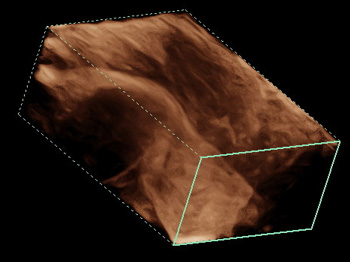

- Программно-технологический комплект 4D: рендеринг поверхности, визуализация полостей, мультипланарная реконструкция, MultiView для ультразвуковой томографии и ряд других функций

4D. Объемное сканирование в реальном времени больше не фантастика, а впечатляющее достижение современных технологий. С помощью сканирования этого типа вы сможете рассмотреть даже самые мелкие детали изображения под любым требуемым для проведения исследов

Трехмерная реконструкция методом «свободной руки». Данный метод позволяет использовать стандартный 2D датчик в ходе диагностики, в то время как аппарат создает полноценное трехмерное изображение на основе полученных во время вашего исследования данных.